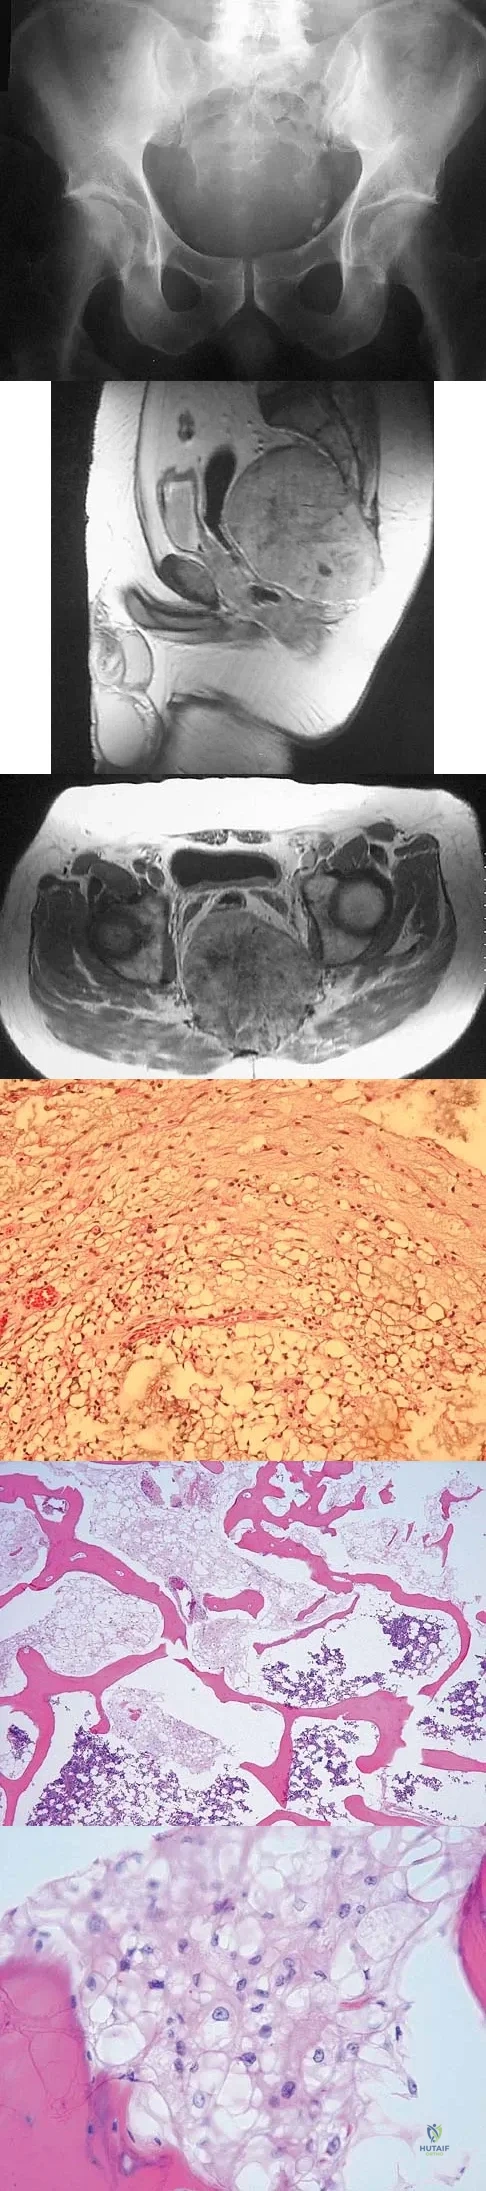

Question 15

A 52-year-old man has had back pain radiating to the left leg for the past 5 weeks. A radiograph, MRI scans, and biopsy specimens are shown in Figures 23a through 23f. What is the most likely diagnosis?

Explanation